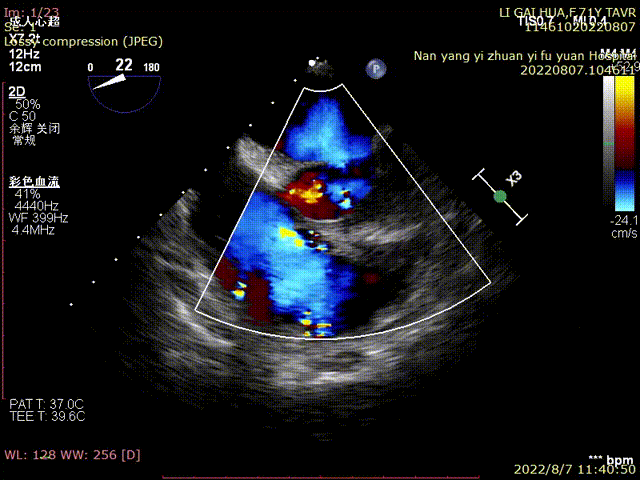

术前TEE超声:

超声明确瓣膜位置

超声评估

瓣膜释放后超声评估:

术中,心外体外循环科郑军医师全程待命。彩超室张俊鹏老师全程跟台,术后行超声探查未见瓣周漏,血压改善。

术中及术后未出现相关并发症,瓣膜植入位置完美,患者症状得到明显改善,手术圆满完成。

TaurusElite AV23瓣膜经过2次调整之后,第3次释放定位位置接近瓣环,心脏瓣膜团队精确定位,零位释放,瓣膜在术前评估的位置牢牢锚定!整个手术过程连贯如行云流水,团队配合默契,操作细致熟练,主动脉根部造影及即时食道超声提示无瓣周漏,TaurusElite首秀成功!